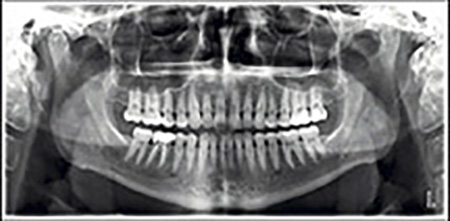

E’ chiamata anche Ortopantomografia o OPT: è un esame a scopo diagnostico delle due arcate dentali complete e del distretto maxillo-facciale. Permette, in un’unica immagine, di avere una visione globale dello stato dei denti, dell’osso mandibolare e mascellare, dei seni mascellari e paranasali, delle articolazioni temporo-mandibolari e dei tessuti gengivali, offrendo all’odontoiatra una visuale completa dell’anatomia del paziente. Questo consente di intervenire con ampio anticipo per affrontare problematiche e risolvere casi che altrimenti rischierebbero di essere trascurati a causa di una diagnosi tardiva.

L’esame si esegue utilizzando un apparecchio radiografico specifico (panoramico o ortopantomografo) che permette di impressionare un sensore digitale (camera CCD) posizionato specularmente alla sorgente che ruota intorno alla testa del paziente.

Il Paziente viene invitato a mordere l’apposito bite (per il corretto allineamento delle arcate) e a posizionare la lingua rilassata e piatta contro il palato alto. Per pochi secondi il paziente non dovrà deglutire e dovrà tenere gli occhi chiusi onde evitare movimenti indesiderati.